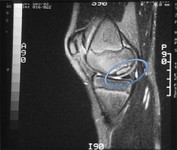

Coronal MRI image of the talus, showing an osteochondral lesion on the medial aspect of the talar dome

Gupta RK, Kansay R, Aggarwal V, et al. Osteochondritis dessicans of the talus in a 26-year-old woman. BMJ Case Reports 2009; doi:10.1136/bcr.06.2008.0091